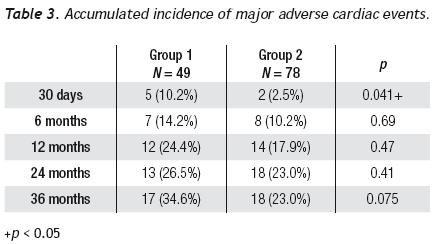

Average follow–up was 27.5 ± 22.2 and 33.6 ± 25.4 months for saphenous vein and native coronary vessel grafts, respectively. The accumulated MACE incidence is shown in Table 3; a difference was observed between groups at 1 month follow–up (10.2% vs. 2.5%, p = 0.041).

A tendency towards a lower MACE incidence was observed in group 2 at 3 years (34.6% vs. 23.0%, p = 0.075). The use of bare–metal stents or DES did not modify the incidence of accumulated MACE. The MACE–free survival by the Kaplan–Meier analysis was 65.0% in the SVG group and 89.1% in the native vessels group (p = 0.024). TVR–free survival was 74.8% and 92.8%, respectively (p = 0.022; Figures 3 and 4). Risk estimation for TVR with the use of DES revealed a reducing–effect tendency, with OR 0.28 (IC 95%, 0.06–1.31, p = 0.09). The TVR–free survival at 36 months in the whole population with the use of DES was 94.1%, compared to 89.8% with bare metal stents (p = 0.64).

The characteristics of a diseased SVG are soft, friable, and voluminous plaques, with a high risk of distal embolization and of periprocedural myocardial infarction, in contrast to the fibrocollagenous content and calcification encountered in native coronary arteries.4 In a report of 1056 consecutive patients with venous grafts, 15% had a > 5x CK–MB rise, leading to a higher mortality rate at one year as compared to patients with normal CK–MB levels (11.7% vs. 4.8%) and corresponds to the most powerful predictor for late mortality.8 In general, PCI of SVGs has been associated to less favorable results as compared with percutaneous intervention of native coronary vessels, with high rates of cardiovascular events, mainly MI.8–11 Our primary end–point —a composite of death, MI, and repeated revascularization— was significantly lower during the first 30 days for the native artery PCI group (10.2°% vs. 2.5%, p = 0.041).